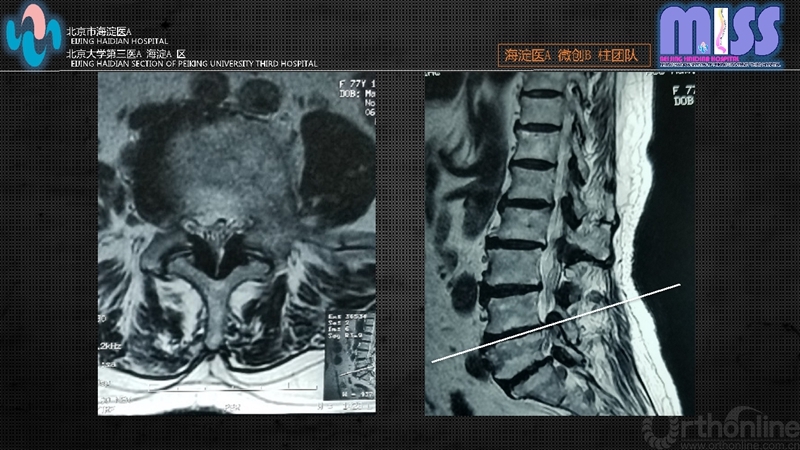

(2)CT和MRI检查证实为腰椎管狭窄,致压物主要为后方肥厚的黄韧带及增生内聚的关节突关节

依据上述标准,2016年1月至2017年6月共34例患者入选,全部采用经皮全内窥镜下经椎板间隙单侧入路双侧减压术,其中男19例,女15例;年龄65~88岁,平均71.9岁;病程0.5~8年,平均2.3年;单侧下肢症状为主8例,双侧下肢症状26例。其中L4/5节段22例,L5/S1节段12例。

③多因素致椎管狭窄,以中央型及侧隐窝狭窄最为常见,中央型狭窄主要由关节突关节内聚增生、黄韧带增生肥厚引起,侧隐窝狭窄主要由关节突关节内侧、椎体与椎间盘的后方压迫引起。